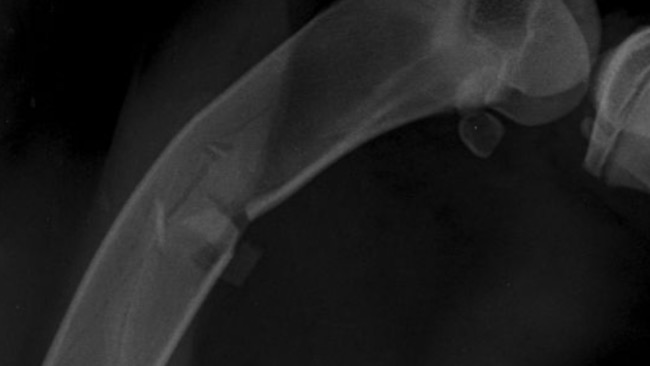

Lekarz zrobił zdjęcia i powiedział coś strasznego — że to złamanie z przemieszczeniem, i że to złamanie patologiczne, które wydarzyło się pod wpływem mojego własnego ciężaru.

To znaczy, że nie tylko trzeba naprawić moją nogę operacją…

ale też znaleźć powód, dlaczego to się stało.